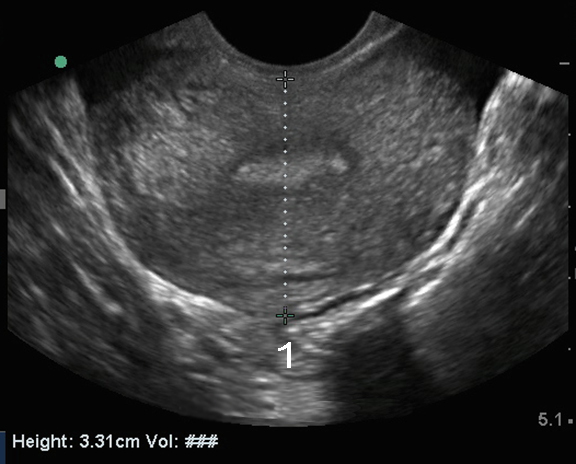

Bild 2: Becken, endovaginaler Ultraschall d. Uterus, transversal